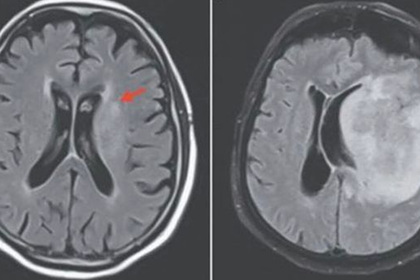

Попавшие в головной мозг микроорганизмы привели к его разжижению. В течение двух недель мужчина испытывал слабость, затем его госпитализировали. Врачи провели сканирование мозга и установили, что у пациента отказала правая часть тела и начались умственные нарушения. Позже мужчина скончался.